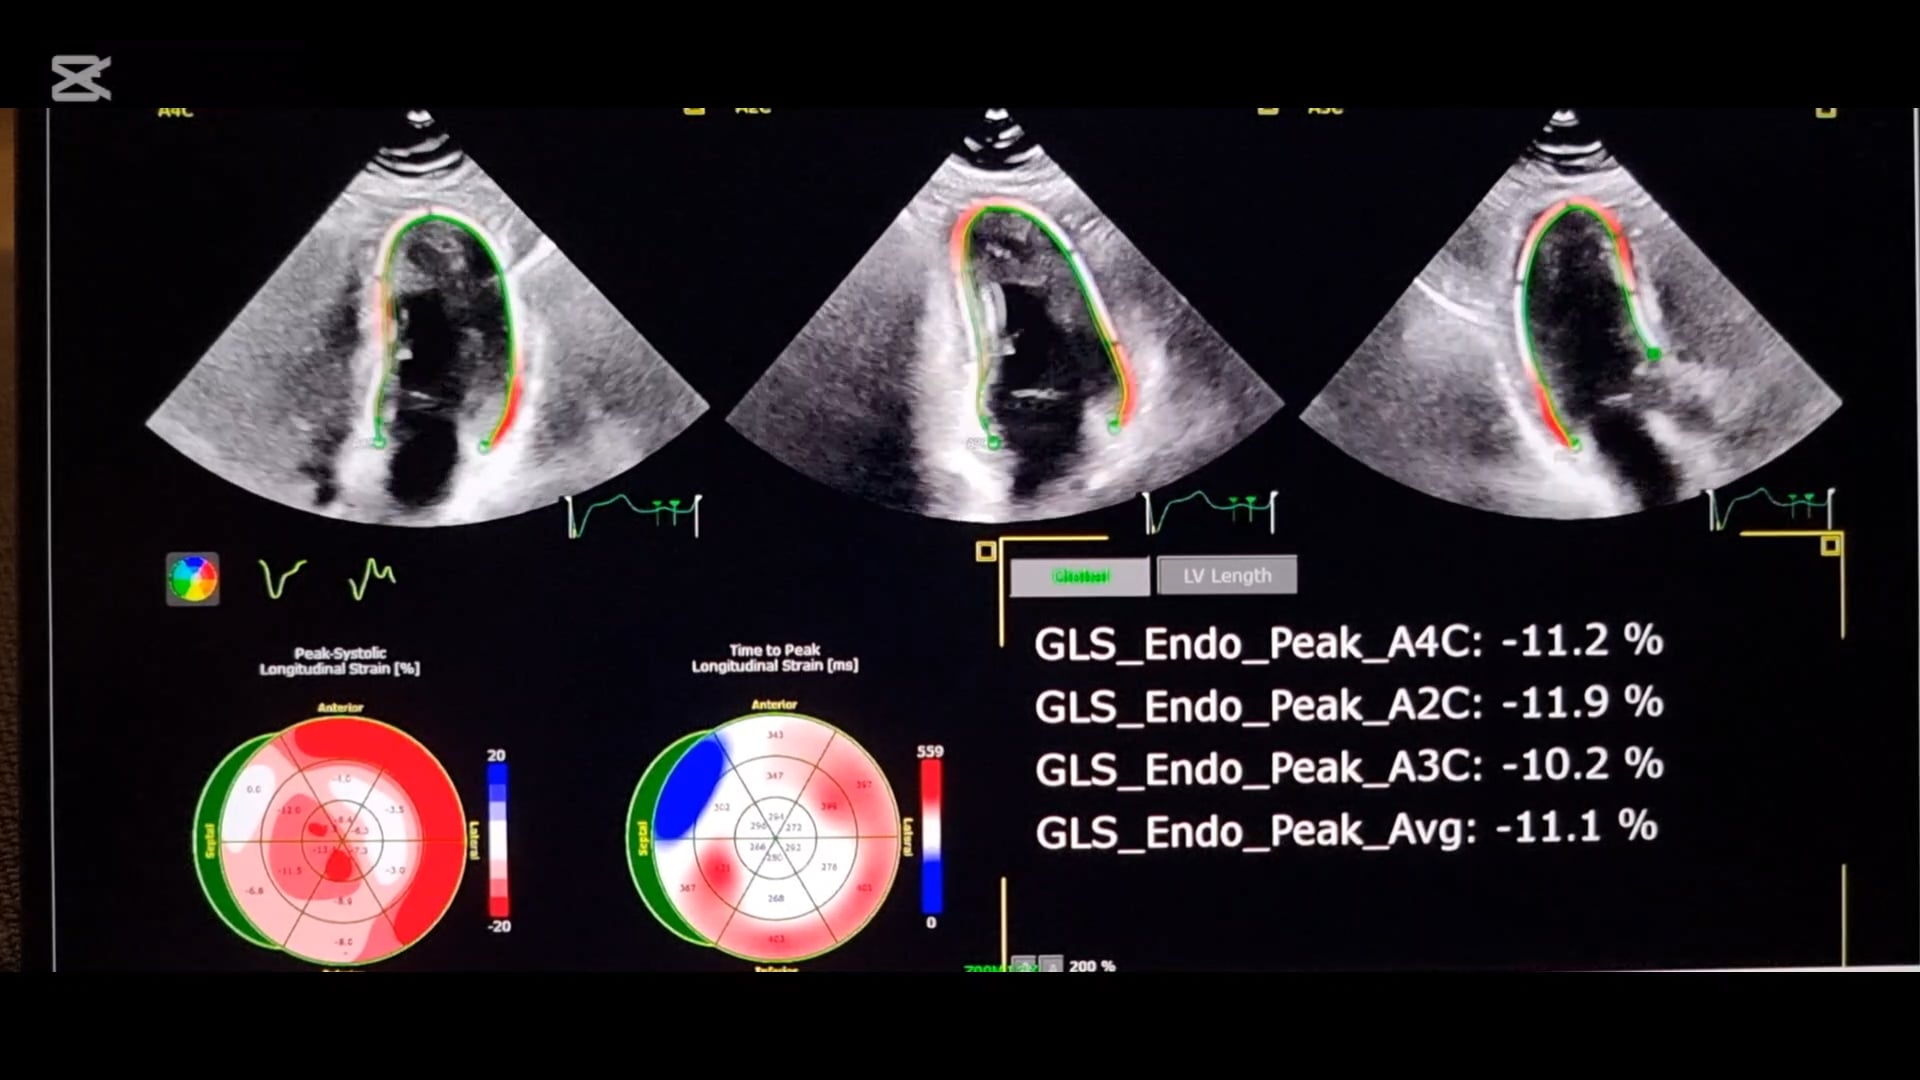

We provide on-site diagnostics including electrocardiography (ECG), 24hr Holter monitoring, 24hr BP monitoring, and echocardiography. We also have strong relationships with the largest radiology providers in Australia, as well as industry leading subspecialists in cardiology and other fields to streamline access to advanced general and cardiac investigations and treatments, including stress testing and CT coronary angiography / calcium scoring.